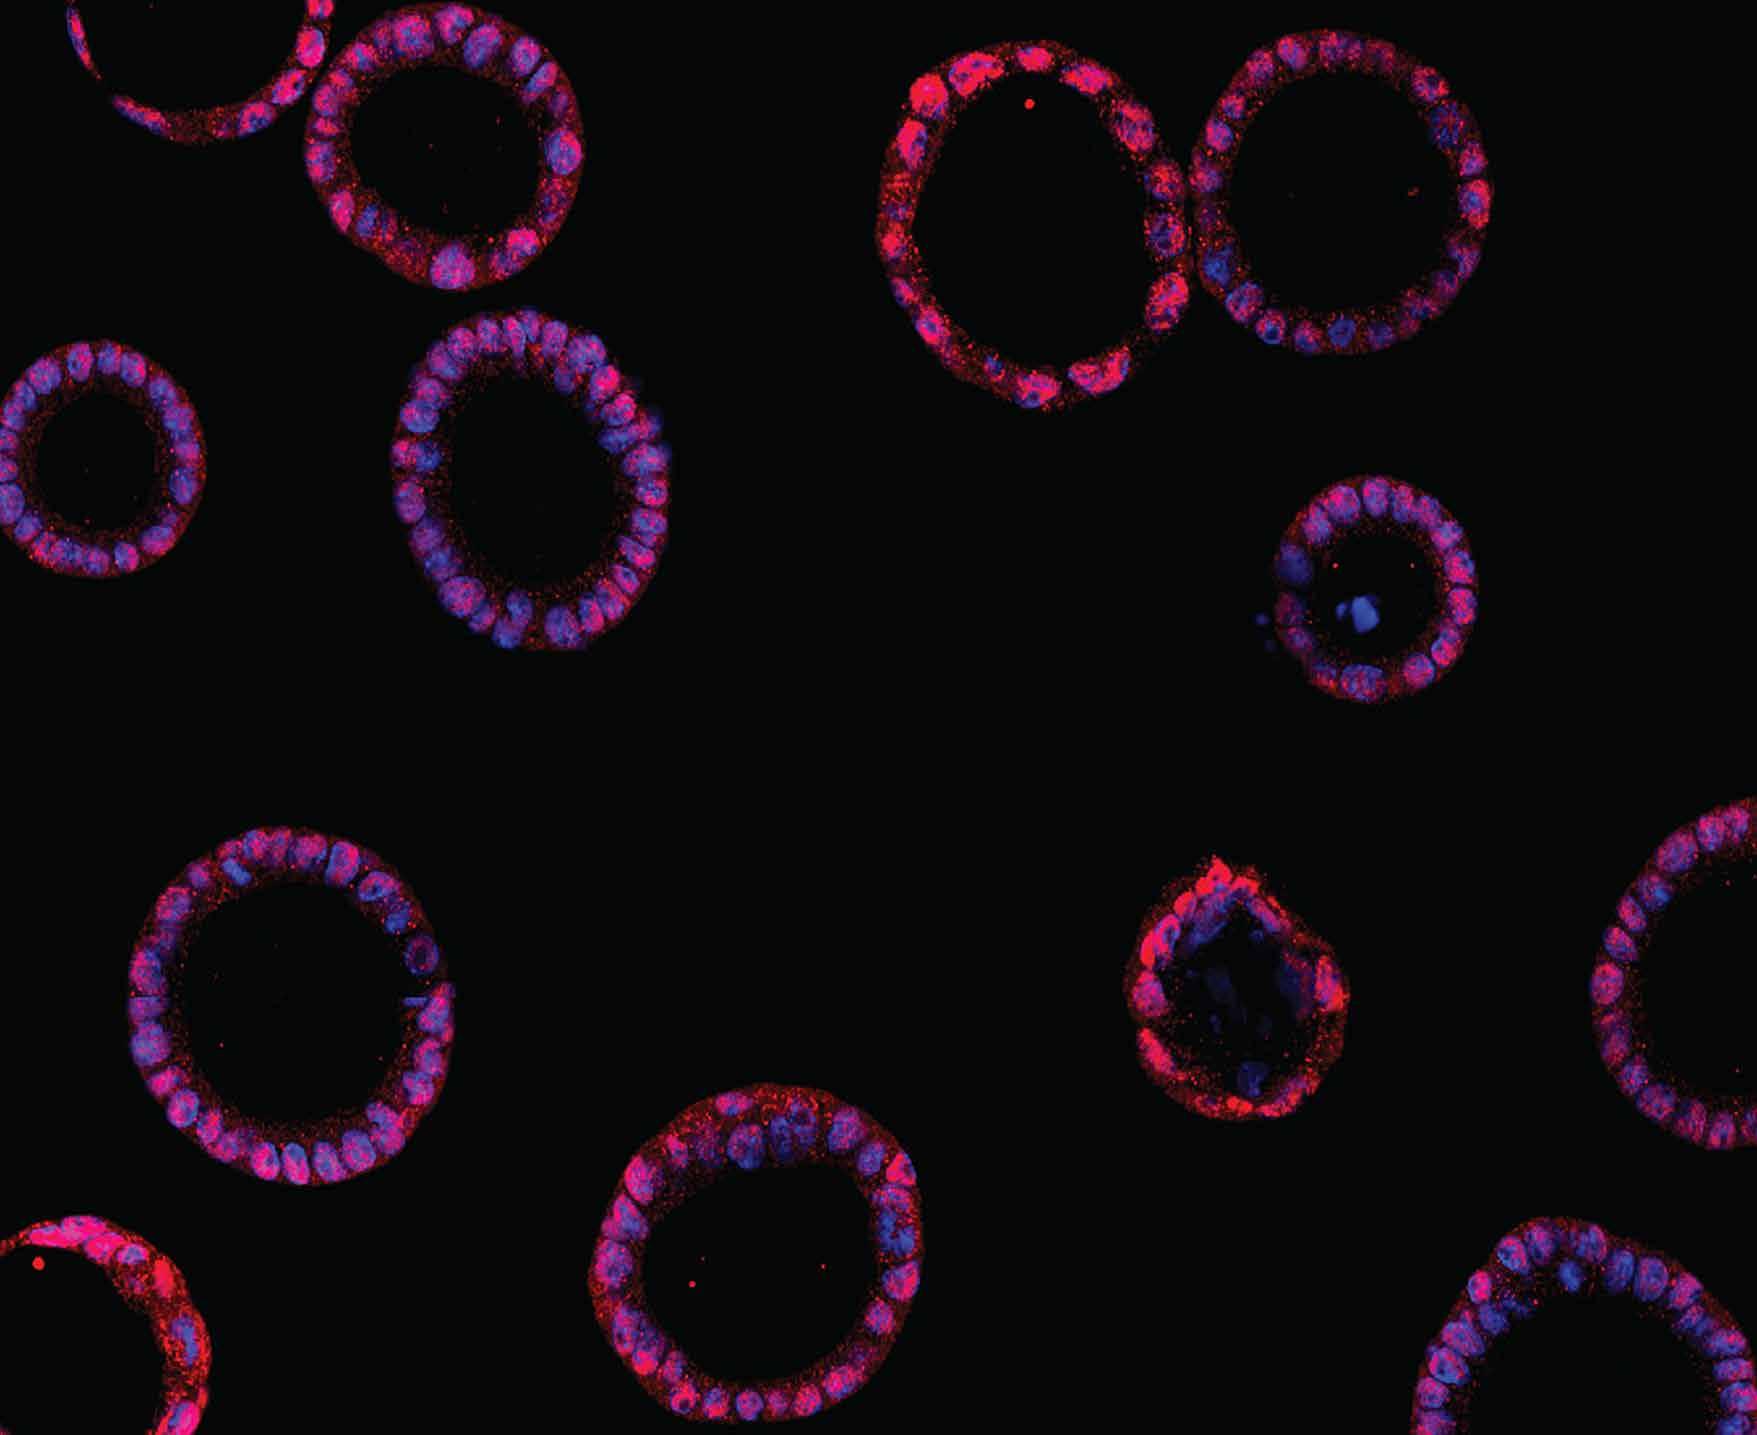

‘Mini-placentas’ shed light on early events that are key for a successful pregnancy

The placenta provides oxygen and nutrients to a growing baby, but its early interactions with a mother’s uterus remain an enigma. Working with lab-grown versions of developing placentas, FMI researchers have shed light on some of the mechanisms underlying the earliest stages of gestation, which are crucial for a successful pregnancy. Understanding how the placenta develops and interacts with the inner lining of the womb may inform future treatments for conditions such as pre-eclampsia — a dangerous pregnancy complication that can put at risk both the mother and her baby’s health.

Magistrati & al., Cell Stem Cell

FMIandNovartislaunchAppliedTissue ModelsCenter

TheFMIandNovartisBiomedicalResearch(BRjoinedforcestoestablishtheFMI-BRAppliedTissueModelsCenter,buildinguponthesuccessfulexampleofthejointlyoperated Cryo-EMcenter.Thenewcenteraimstofostercollaborationbetweenthetwoorganizationsandadvancebiomedicalresearchwithcomplexcellularmodelssuchasorganoids powerfultoolstomimicbiologyanddiseaseprocesses.Sinceworkingwiththese modelsrequiresspecializedinfrastructureandknow-how,theFMIandNovartishave investedinsharedlabswherescientistscanex-changeknowledgeandusestate-of-theartequipment.